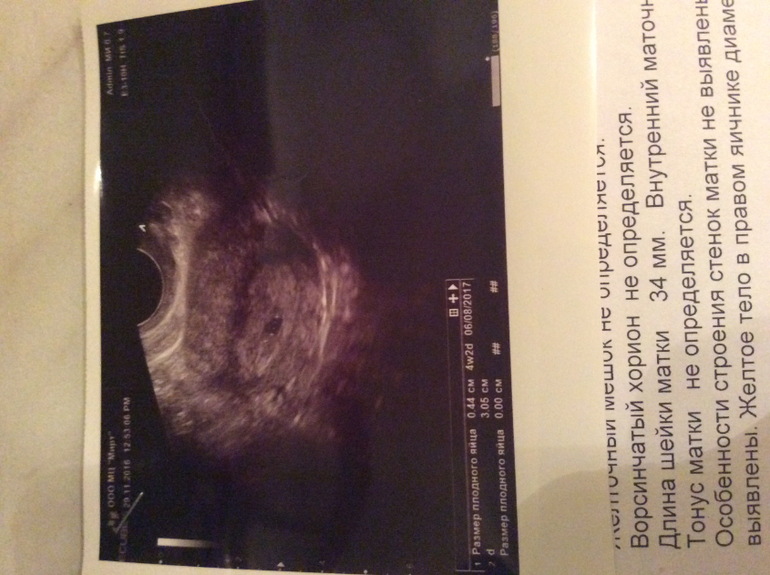

До последнего не верила, то думала кажется, то полоски недостаточно яркие, та хгч слишком маленький, то тянет сбоку по любому внематочная! Девочки, это такой кайф после 3х лет попыток, на узи наконец то услышать что плодное яйцо есть и оно в матке!! До сих пор отхожу😀😀😀